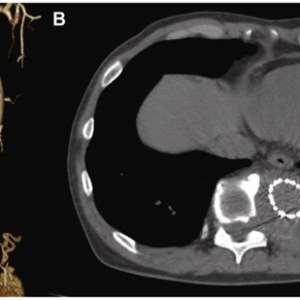

Процедура была проведена медсестрой и ординатором-неонатологом. Рентгенография, проведенная после процедуры, показала, что катетер расположен внутри сердца, катетер был подтянут на 1,5 см (рис.1).

Процедура была проведена медсестрой и ординатором-неонатологом. Рентгенография, проведенная после процедуры, показала, что катетер расположен внутри сердца, катетер был подтянут на 1,5 см (рис.1).

Обратился в отделение неотложной помощи с жалобами на постепенно усиливающуюся боль в спине, которая беспокоила его в течение месяца.

В анамнезе травма грудного отдела позвоночника, полученная в возрасте 42 лет, которая привела к параплегии нижних конечностей и потребовала установки позвоночной пластины. В возрасте 45 лет ему была проведена экстренная операция TEVAR по поводу разрыва инфицированной аневризмы нисходящей части грудной аорты с использованием одностентного трансплантата Najuta (Kawasumi Labo, Inc., Токио, Япония), который состоит из Z-образного стента и ткани из политетрафторэтилена (ПТФЭ). Проведена антибиотикотерапия.

После выздоровления пациент находился под наблюдением в амбулаторных условиях. В течение периода наблюдения его артериальное давление поддерживалось на уровне примерно 130 мм рт. ст. без эпизодов тяжелой гипертензии.

На момент обращения гемодинамические показатели пациента были стабильными: артериальное давление составляло 140/95 мм рт. ст., а частота сердечных сокращений — 110 ударов в минуту.

При осмотре была обнаружена пульсирующая опухоль, пальпируемая примерно на расстоянии трёх пальцев ниже кончика левой лопатки.

Обратился в отделение неотложной помощи с жалобами на постепенно усиливающуюся боль в спине, которая беспокоила его в течение месяца.

В анамнезе травма грудного отдела позвоночника, полученная в возрасте 42 лет, которая привела к параплегии нижних конечностей и потребовала установки позвоночной пластины. В возрасте 45 лет ему была проведена экстренная операция TEVAR по поводу разрыва инфицированной аневризмы нисходящей части грудной аорты с использованием одностентного трансплантата Najuta (Kawasumi Labo, Inc., Токио, Япония), который состоит из Z-образного стента и ткани из политетрафторэтилена (ПТФЭ). Проведена антибиотикотерапия.

После выздоровления пациент находился под наблюдением в амбулаторных условиях. В течение периода наблюдения его артериальное давление поддерживалось на уровне примерно 130 мм рт. ст. без эпизодов тяжелой гипертензии.

На момент обращения гемодинамические показатели пациента были стабильными: артериальное давление составляло 140/95 мм рт. ст., а частота сердечных сокращений — 110 ударов в минуту.

При осмотре была обнаружена пульсирующая опухоль, пальпируемая примерно на расстоянии трёх пальцев ниже кончика левой лопатки.